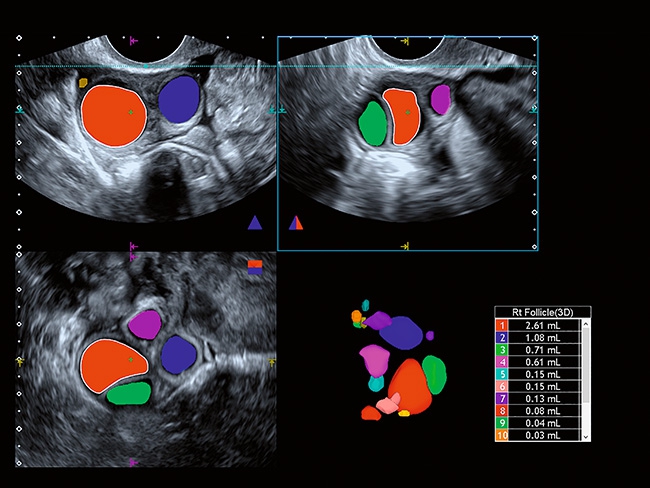

Отличная цветопередача с высокой детализацией и четкостью изображения. Устройство подходит для профессионального использования в частных кабинетах и крупных медицинских центрах. Комплектация сканера применима для самых разных исследований. Широкий диапазон прикладного клинического программного обеспечения высокоэффективен для общих исследований, сердечно-сосудистых, гинекологических, ортопедических, урологических.

Aplio a550 может работать с линейным матричным датчиком и поддерживает новейшие монокристаллические датчики. Также Aplio a550 поддерживает большое количество дополнительных опций, таких как - SMI, Компрессионная эластография, Эластография сдвижной волны, Smart Fusion, исследования с использованием контраста (CEUS), 3D реконструкции в реальном времени (4D), функции автоматической оценки подвижности миокарда и фракции выброса.

Общая визуализация, Гинекология и акушерство, УЗИ для кардиологии

Гинекология:

Да